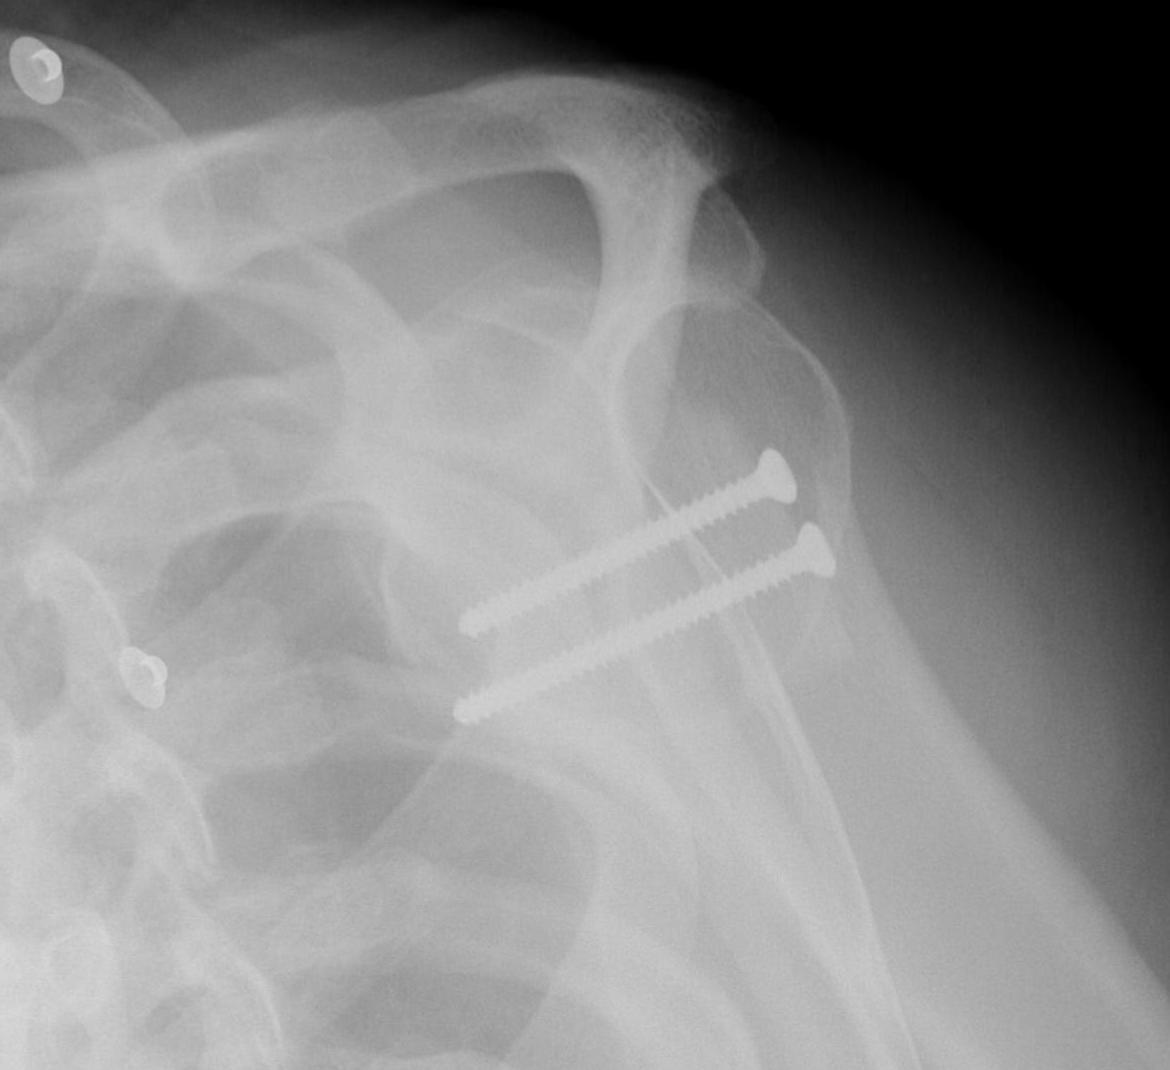

Beach chair or lateral position

- posterior approach / L shaped incision

- elevate or detach deltoid from scapular spine

- detach infraspinatus

- iliac crest or distal tibial allograft

Identify and elevate deltoid / detach from scapular spine / identify infraspinatus

Identify interval between infraspinatus and teres minor, detach and reflect infraspinatus to expose posterior capsule and glenoid

- osteotomy parallel to articular surface, 1.5 cm from articular surface

- preserves anterior 1 cm of glenoid to prevent iatrogenic fractures

- open 4 - 5 mm and insert bone graft

- +/- fixation